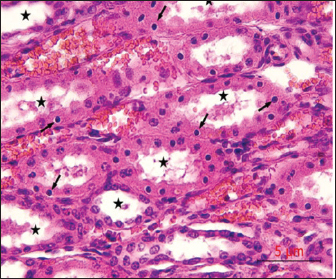

Post-mortem examinations of the dead horses infected with M. haemofelis revealed signs of overall emaciation in the affected animals, paleness of internal organs (Fig. 5), and prominent splenomegaly. The liver, kidneys were enlarged; however, the heart showed white patches. Moreover, histopathological changes were characterized by different histopathological changes of eosinophilic degeneration of cardiac muscle fibers, accompanied by atrophy in some fibers, with bleeding between fibers, besides atrophic glomeruli, accompanied with the dilatation of renal tubules in the kidneys, as well as marked reduction in the proportion of white pulp of splenic tissue and degenerative changes in the cytoplasm of hepatocytes, accompanied by nuclear alterations characterized by loss of chromatin content in the hepatic tissue (Figs. 69).

Fig. 9. sections demonstrated degenerative changes in the cytoplasm of hepatocytes (arrows), accompanied by nuclear alterations characterized by loss of chromatin content (arrowhead), H&E, 40x. Scale bar=5µm.